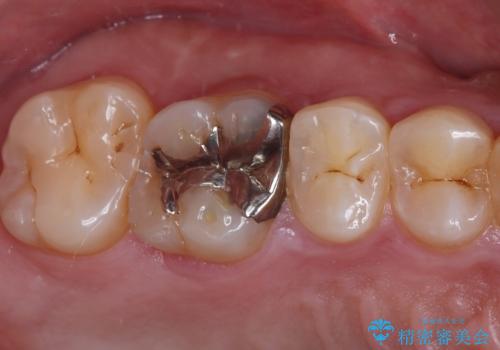

- 保険診療で治療した銀歯のやり替え希望の患者様です。

銀歯とその下の虫歯を除去し、形を整え、精度の良いシリコーンによる型どりを行いました。